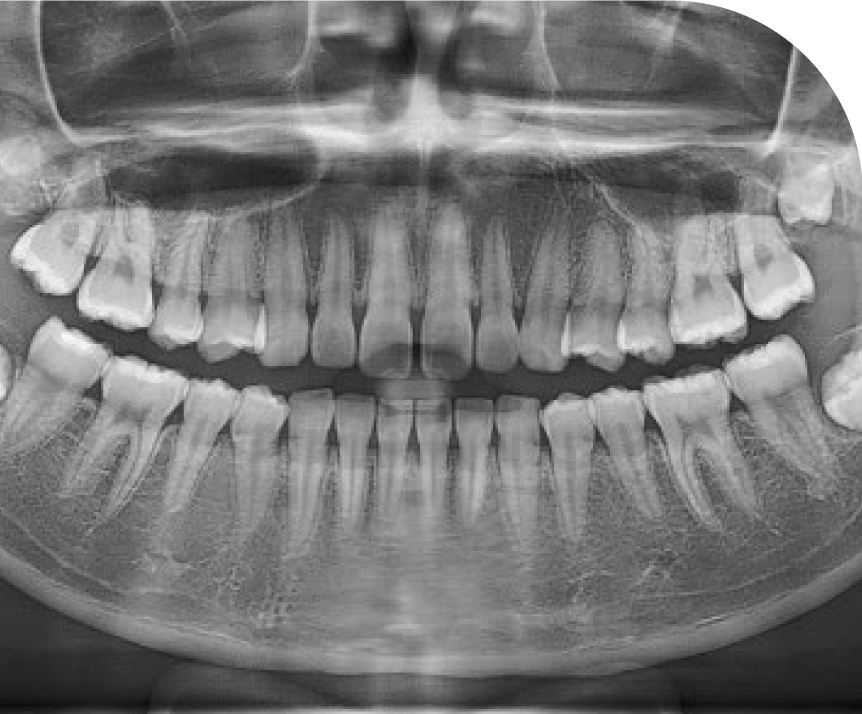

Clear Panorama

Comprehensive Dental Imaging

AMF (Adaptative Moving Focus) technology selects the optimal image layer to provide clear panoramic images, making it easy to identify the patient’s periodontal condition and lesion location.